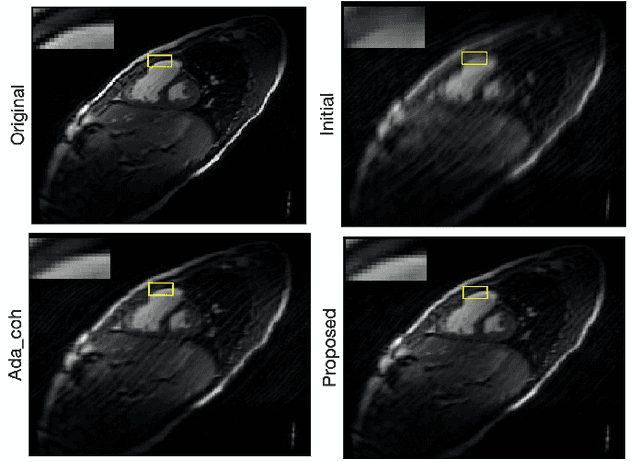

Magnetic resonance imaging (MRI) is a powerful imaging modality that revolutionizes medicine and biology. The imaging speed of high-dimensional MRI is often limited, which constrains its practical utility. Recently, low-rank tensor models have been exploited to enable fast MR imaging with sparse sampling. Most existing methods use some pre-defined sampling design, and active sensing has not been explored for low-rank tensor imaging. In this paper, we introduce an active low-rank tensor model for fast MR imaging.We propose an active sampling method based on a Query-by-Committee model, making use of the benefits of low-rank tensor structure. Numerical experiments on a 3-D MRI data set demonstrate the effectiveness of the proposed method.